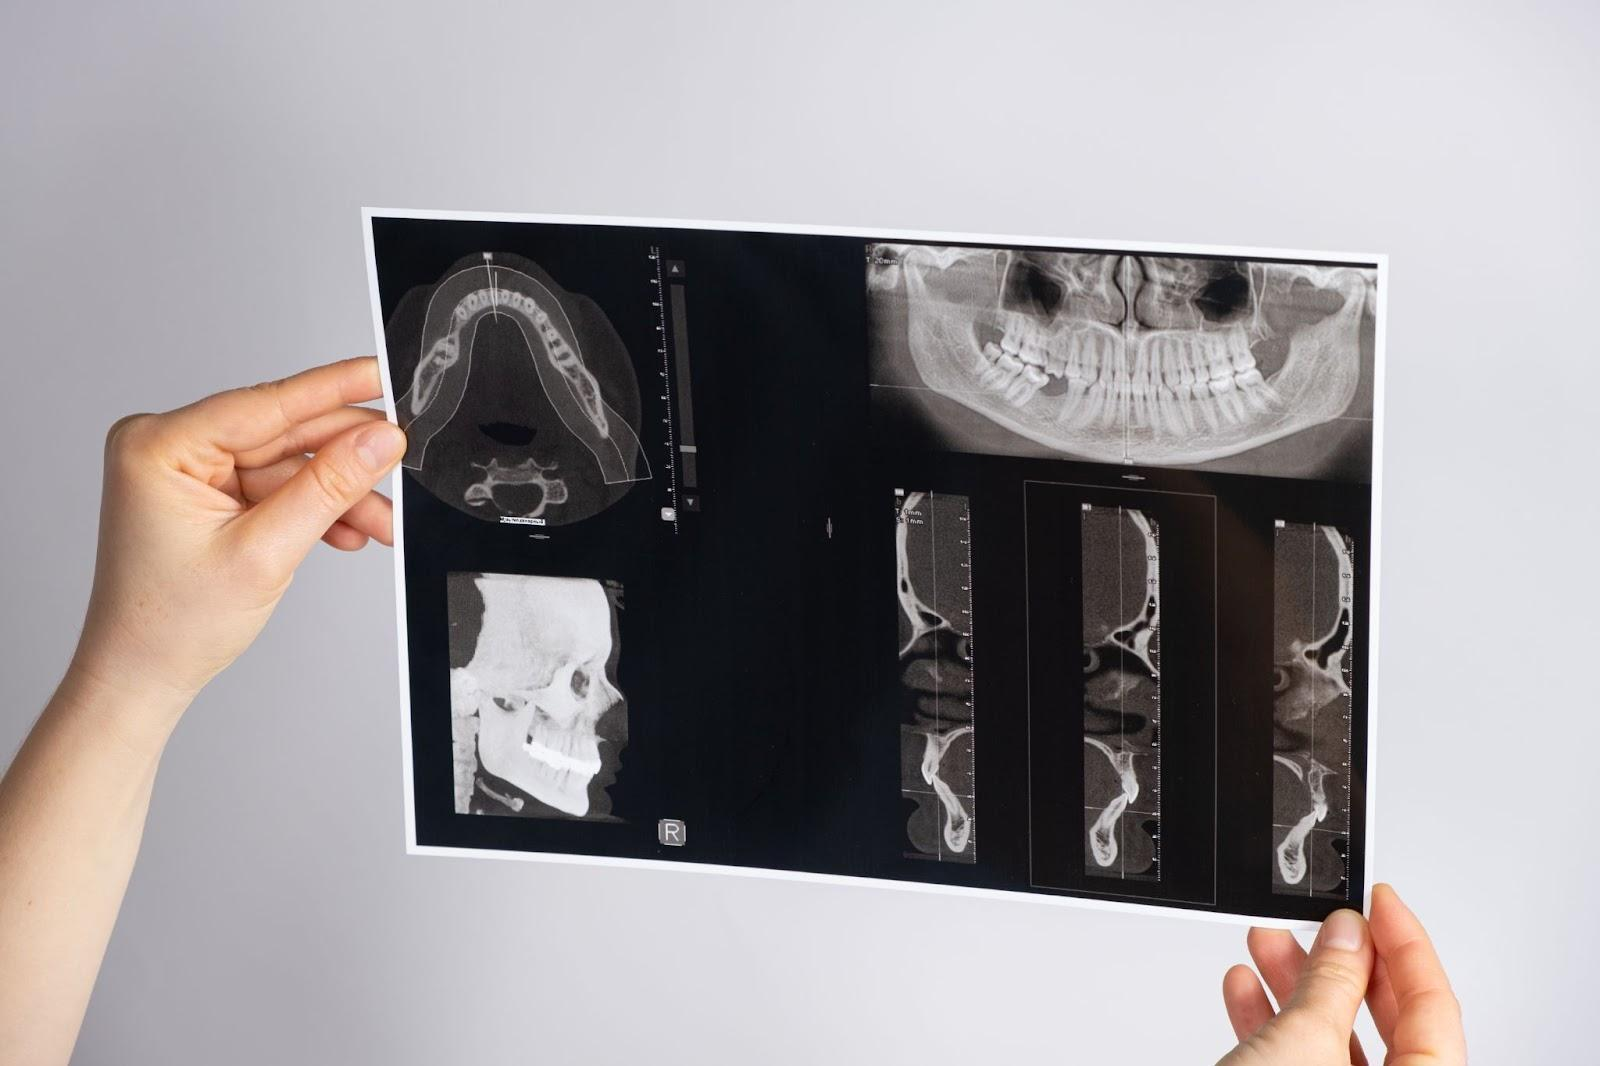

歯科用CTは歯や顎の状態を立体的に撮影し、より正確な診断と治療計画を立てるための検査機器です。

通常のレントゲンでは2Dでしか確認できない部分を、歯科用CTでは3D画像として表示できるため、歯や骨の内部構造、神経や血管の位置まで詳しく把握できます。

歯科用CTは『コーンビーム方式』という短時間スキャンを採用しており、撮影はわずか数秒で終了します。

さらに歯科用CTは放射線量が少なく、安全性が高いとされる検査です。

一般的な医科用CTの被ばく量を1とすると、歯科用CTはその約10分の1程度に抑えられています。